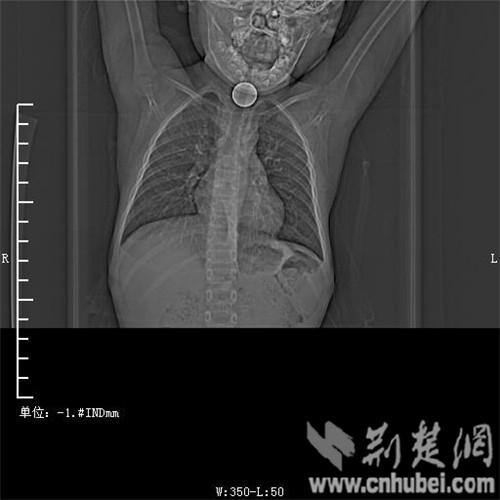

圖為:硬幣卡在了陽陽的喉部

消化內(nèi)主任方向明告訴記者,孩子送來時(shí)已經(jīng)是晚上8點(diǎn)15分,醫(yī)護(hù)人員立即給孩子拍胸部CT確定硬幣的位置,8點(diǎn)30分,方向明通過胃鏡下食管異物取出術(shù),成功的將這枚一元硬幣取了出來。1月5日上午,陽陽順利出院,醫(yī)生護(hù)士在他出院時(shí)不斷告訴他,以后千萬不要吞含異物。